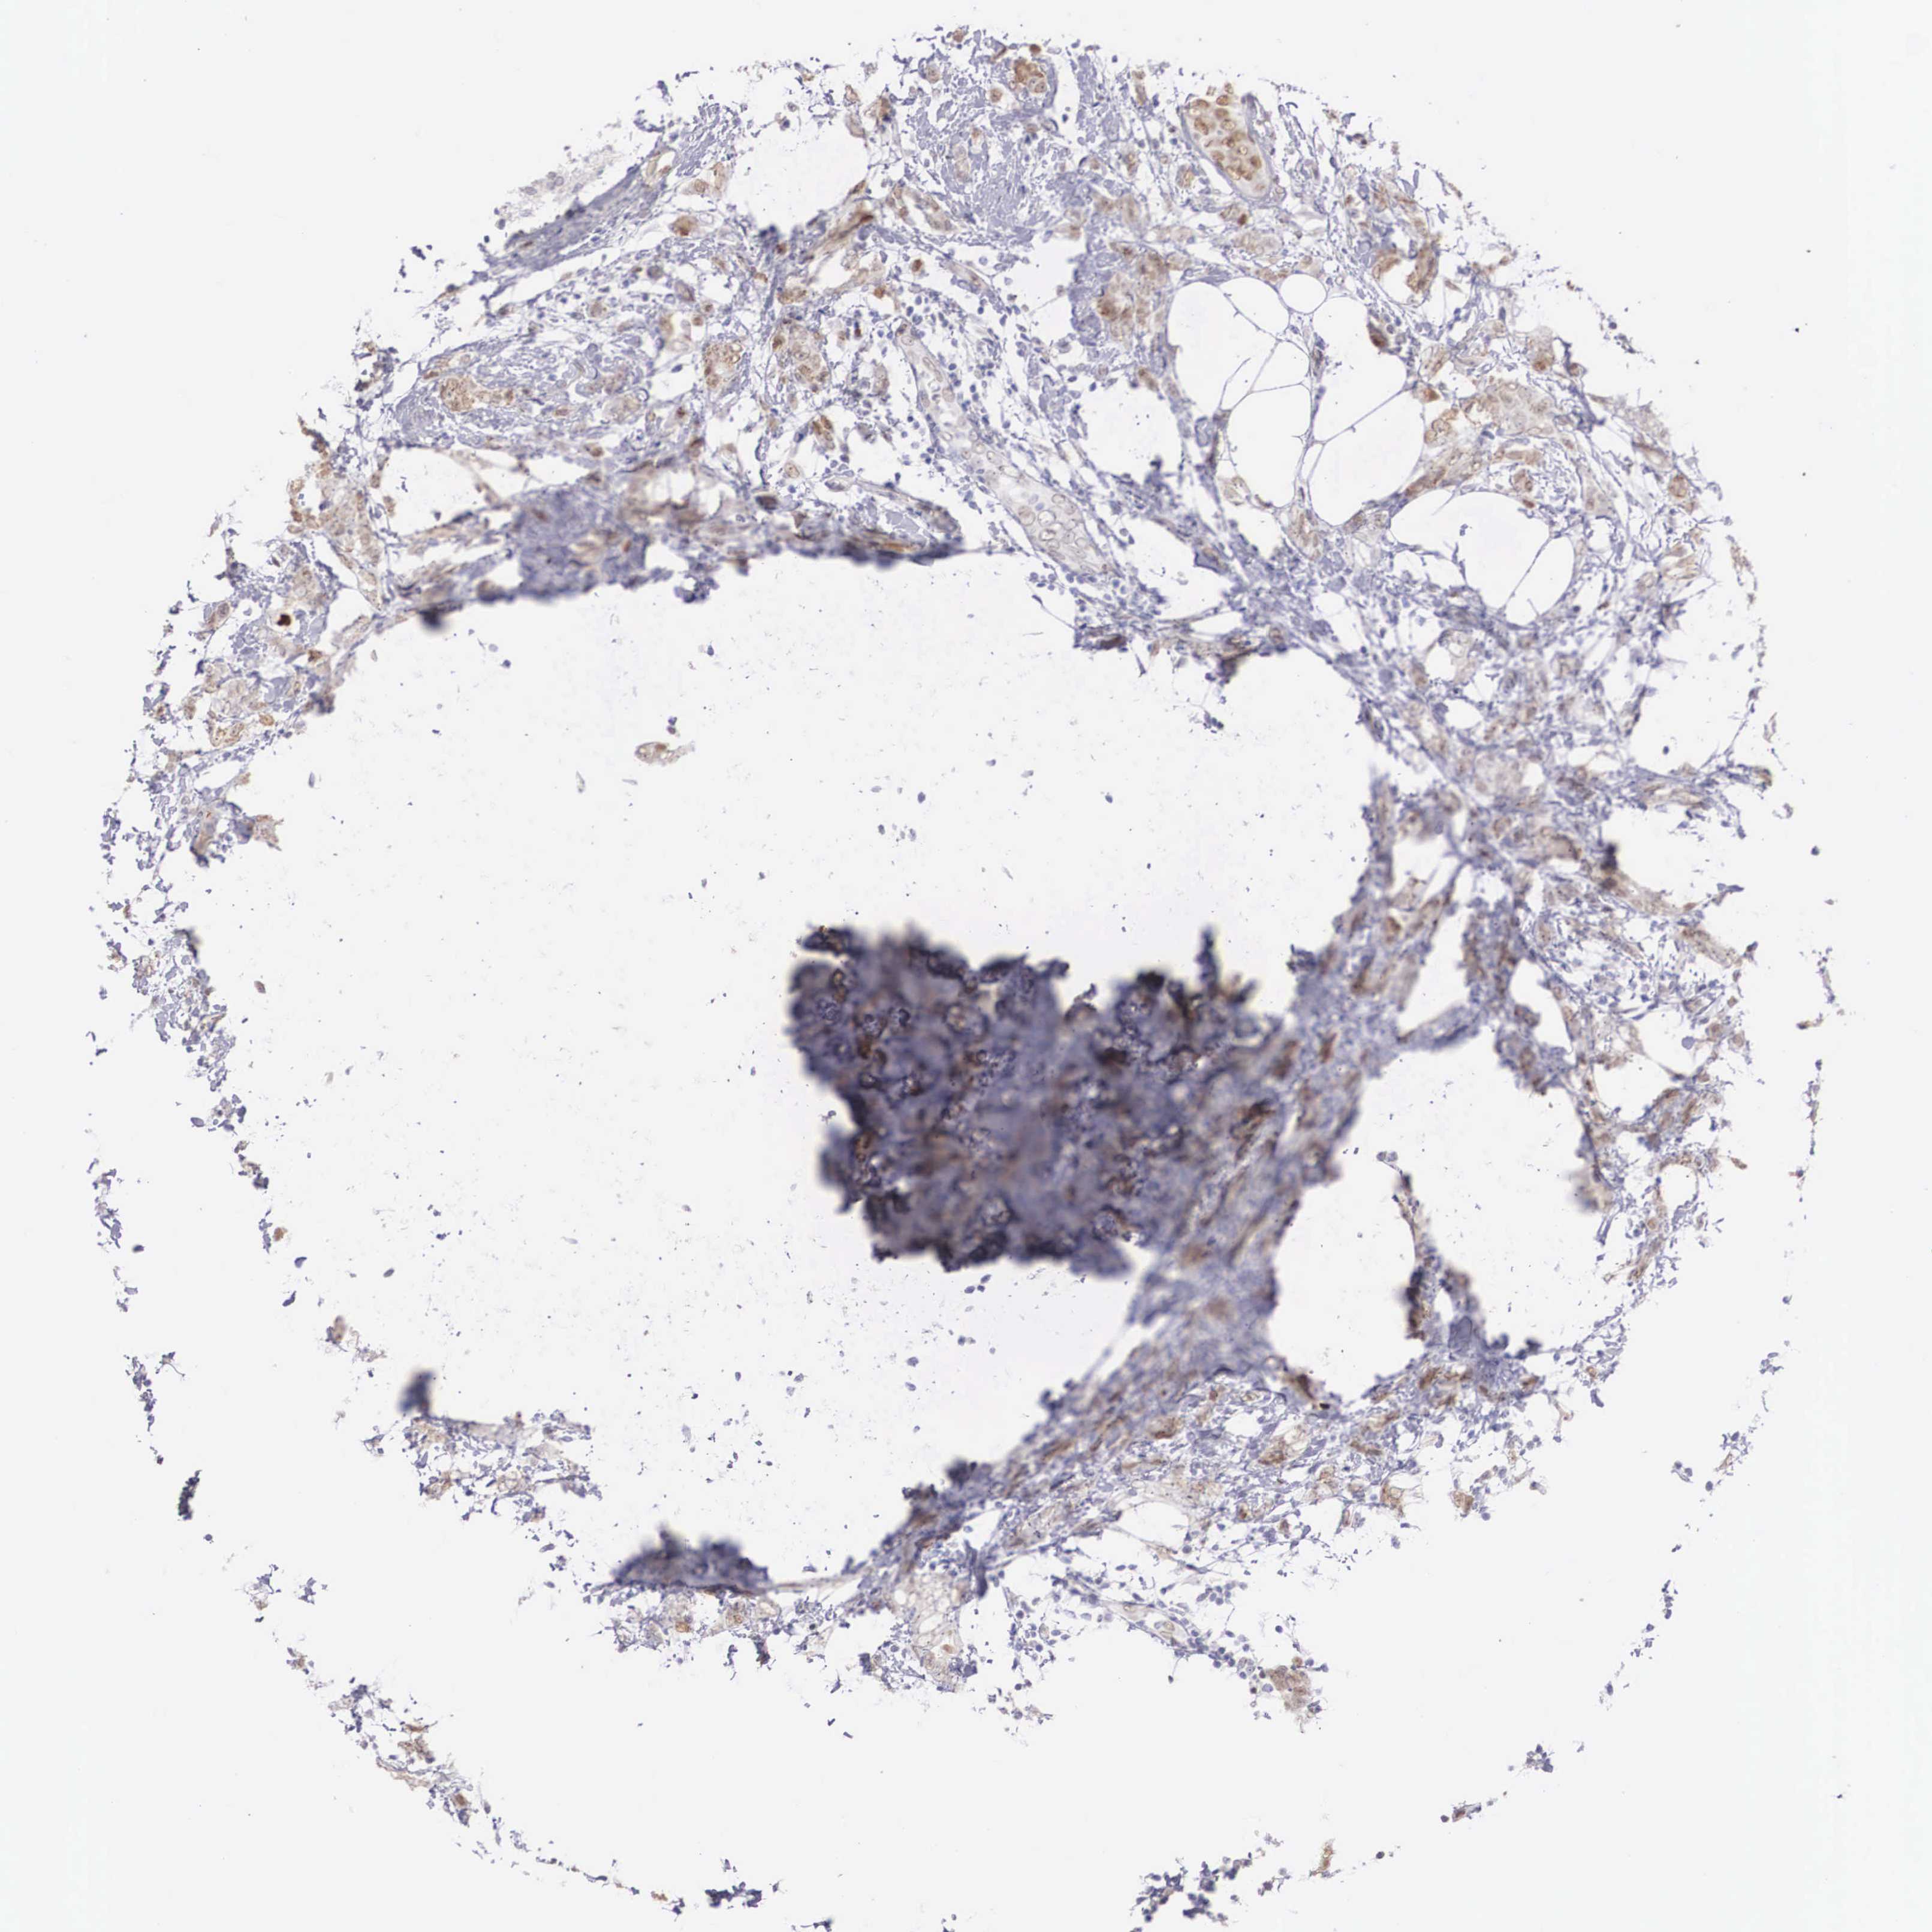

BRCA TCGA BRCA VALIDATION PROTEIN EXPRESSION